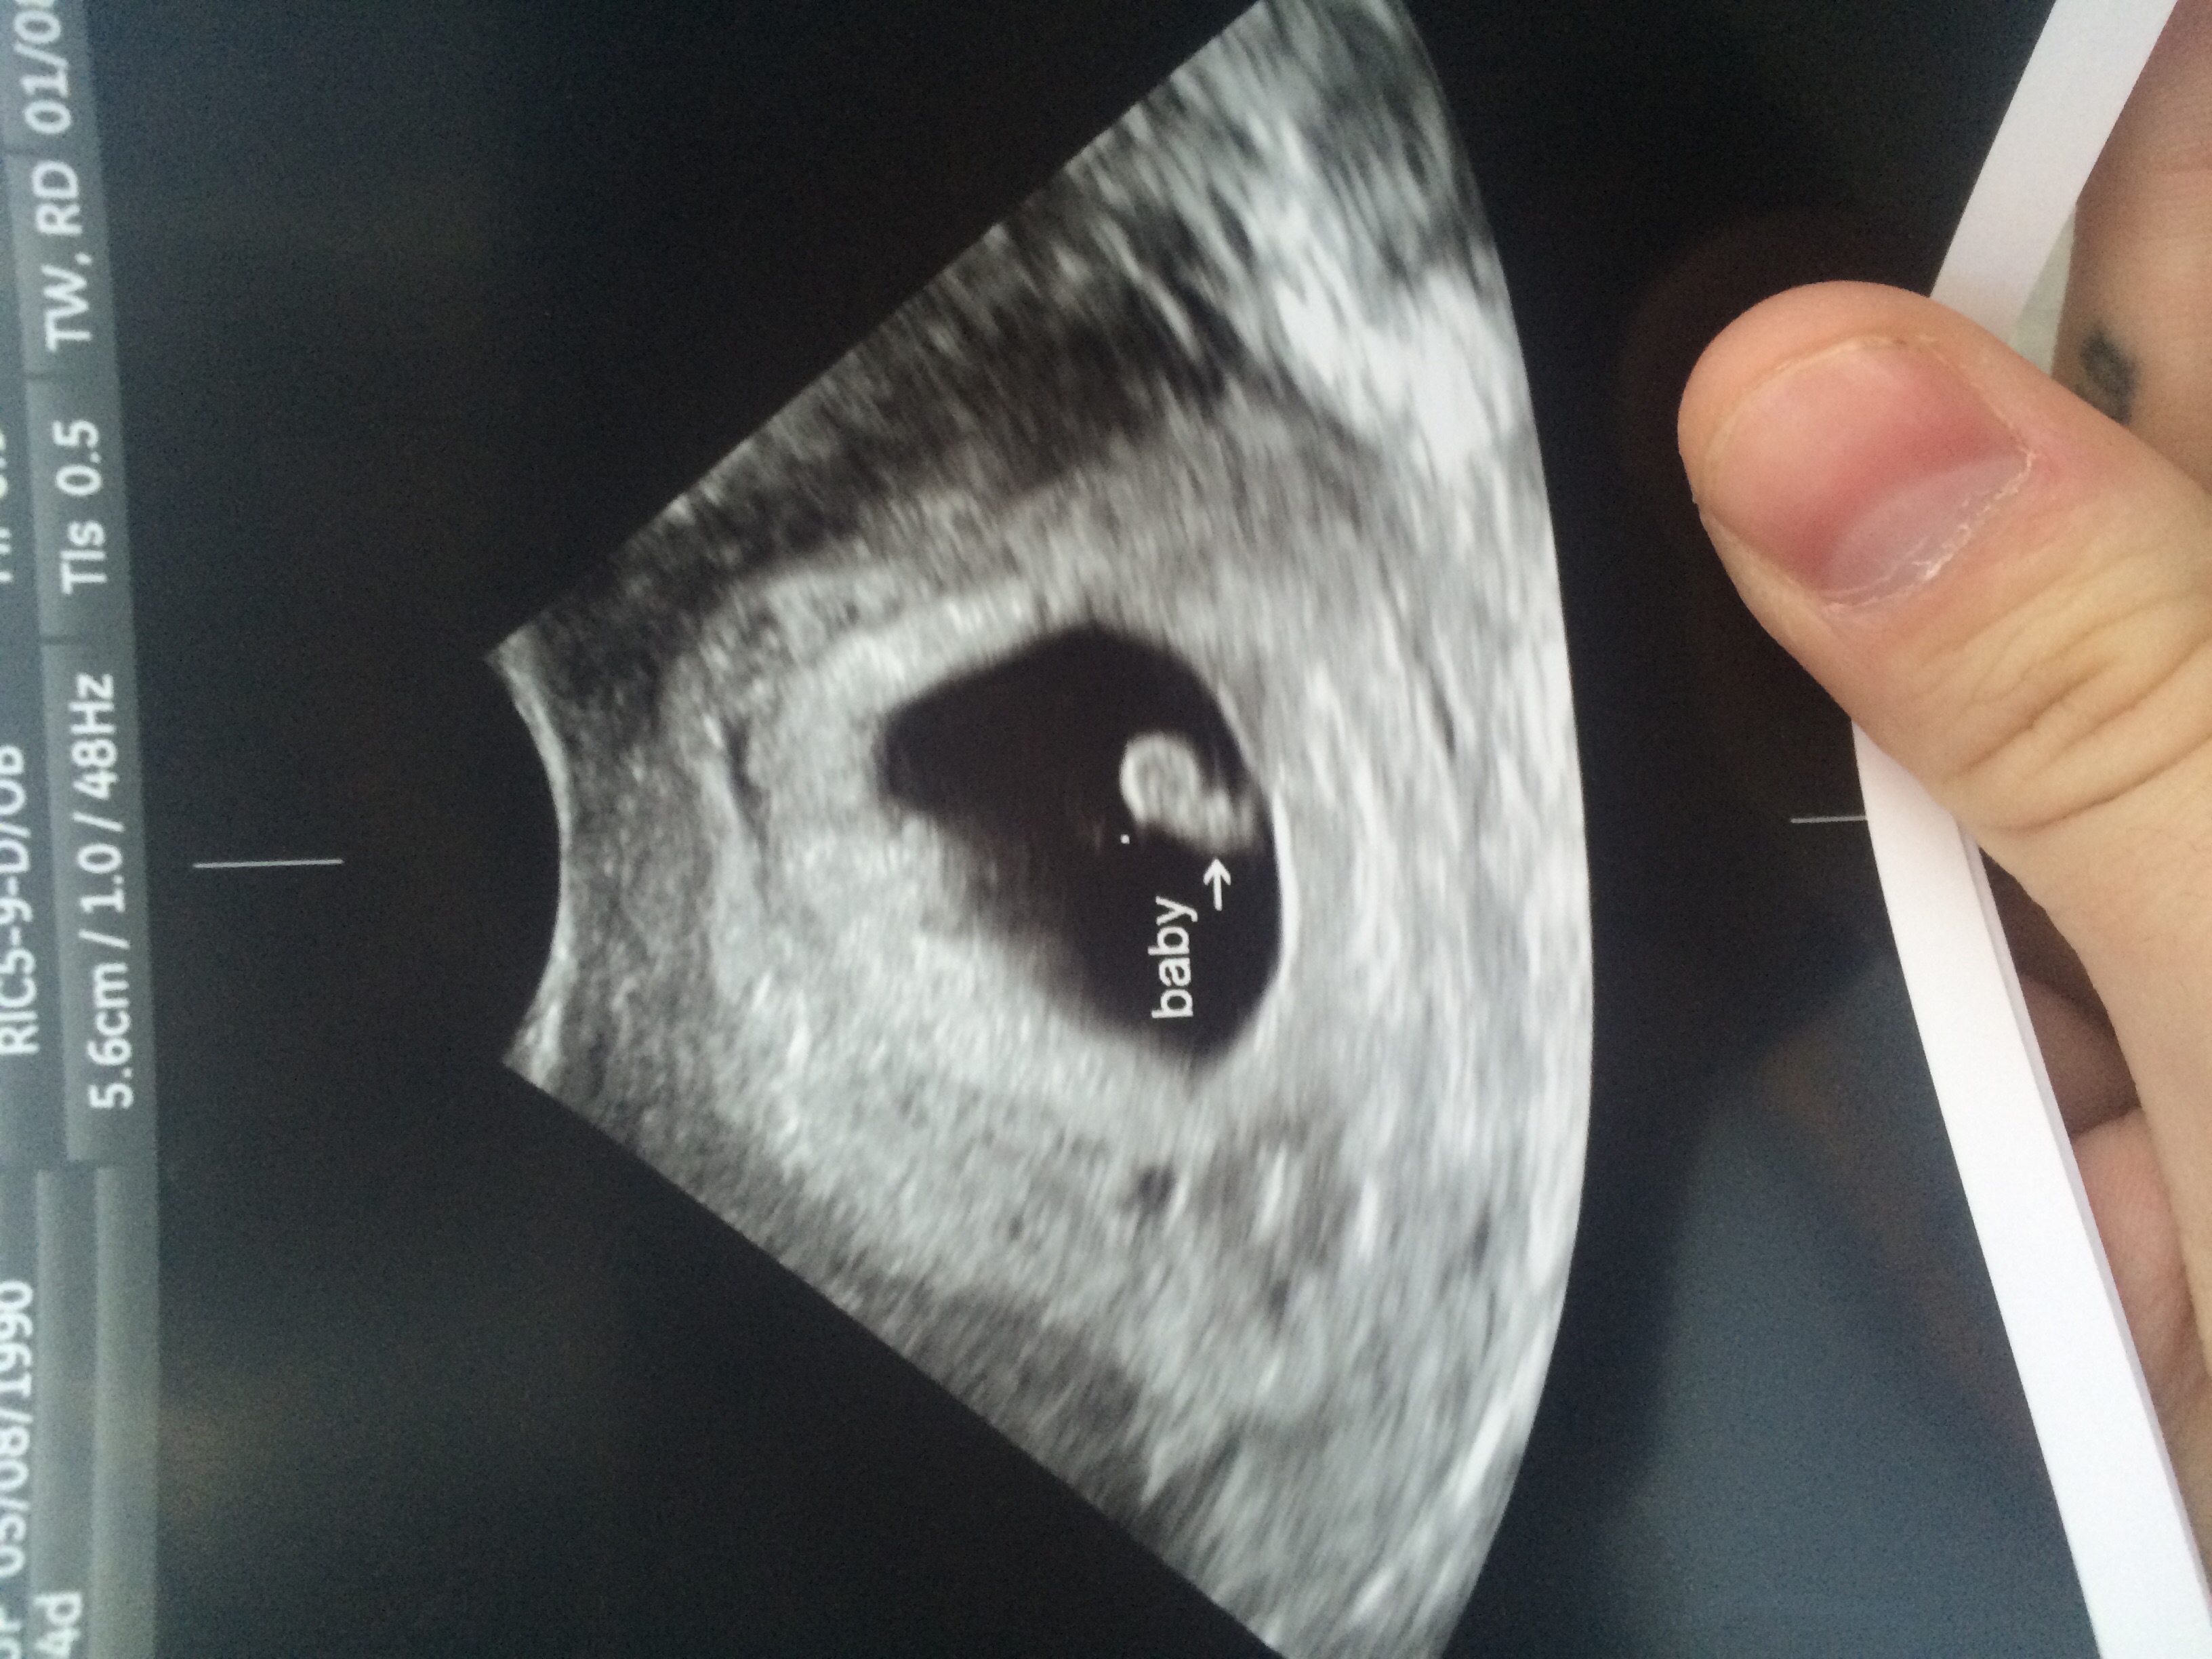

We got to see our little beans heart beat today! It was amazing! I was also discharged from my RE today so that's super exciting!

• Yay! What a cute little blob you have there!

• That's awesome!! Congrats!! This is my 5 1/2 wk ultrasound. Have another ultrasound Wednesday for my 6 1/2 week so hopefully I'll be released from My RE :) Can't wait to see the heartbeat and actual baby!!

• It's our first and DH/I saw the heartbeat yesterday. Amazing! 109 beats per minute!

I've never seen such a thing...that fluttering little thing!